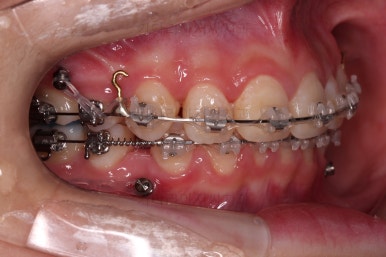

사용한 장치 : 자가결찰 세라믹(엠파워 클리어, Empower clear) + 미니스크류

초진 시 입안의 모습입니다.

위아랫니가 많이 삐뚤진 않는데 뭔가 이상하죠?

어금니 맞물림은 지그재그로 잘 맞물려 있는데 위아래 앞니는 서로 앞뒤로 매우 멀죠.

비밀은 매우 자연스러워 보이지만 아래 앞니 2개가 선천 결손인 상태였습니다.

앞니끼리 맞물리지 않다보니 아래 앞니는 점점 솟구쳐 과개교합(깊게 맞물려 아래 앞니가 거의 보이지 않는 현상)이 되게 됩니다.

치아 갯수를 맞추고 튀어나온 앞니를 넣기 위해서 윗니 중간의 작은 어금니를 발치를 했고요.

아래는 통째로 앞으로 끌고 나오기로 했습니다.